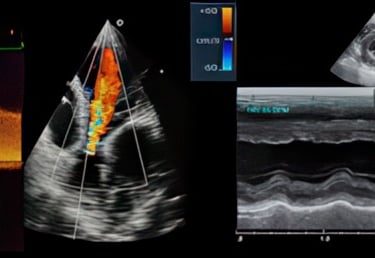

Echocardiography is not just another imaging modality—it's a dynamic, physiologic tool that informs assessment of function, hemodynamics, and real-time clinical response. This hands-on cardiac course matters because it teaches you to acquire meaningful views under real conditions, interpret Doppler and motion patterns with purpose, and integrate those findings into urgent and routine cardiovascular decision-making. You walk away with competence you can use immediately at the bedside, not just a stack of saved clips.

Apply Doppler techniques intentionally to assess flow, pressure relationships, and hemodynamics rather than relying on presets

Evaluate ventricular function, chamber size, wall motion, and loading conditions with clinical context

Assess valvular anatomy and function using image-based reasoning instead of rote measurements